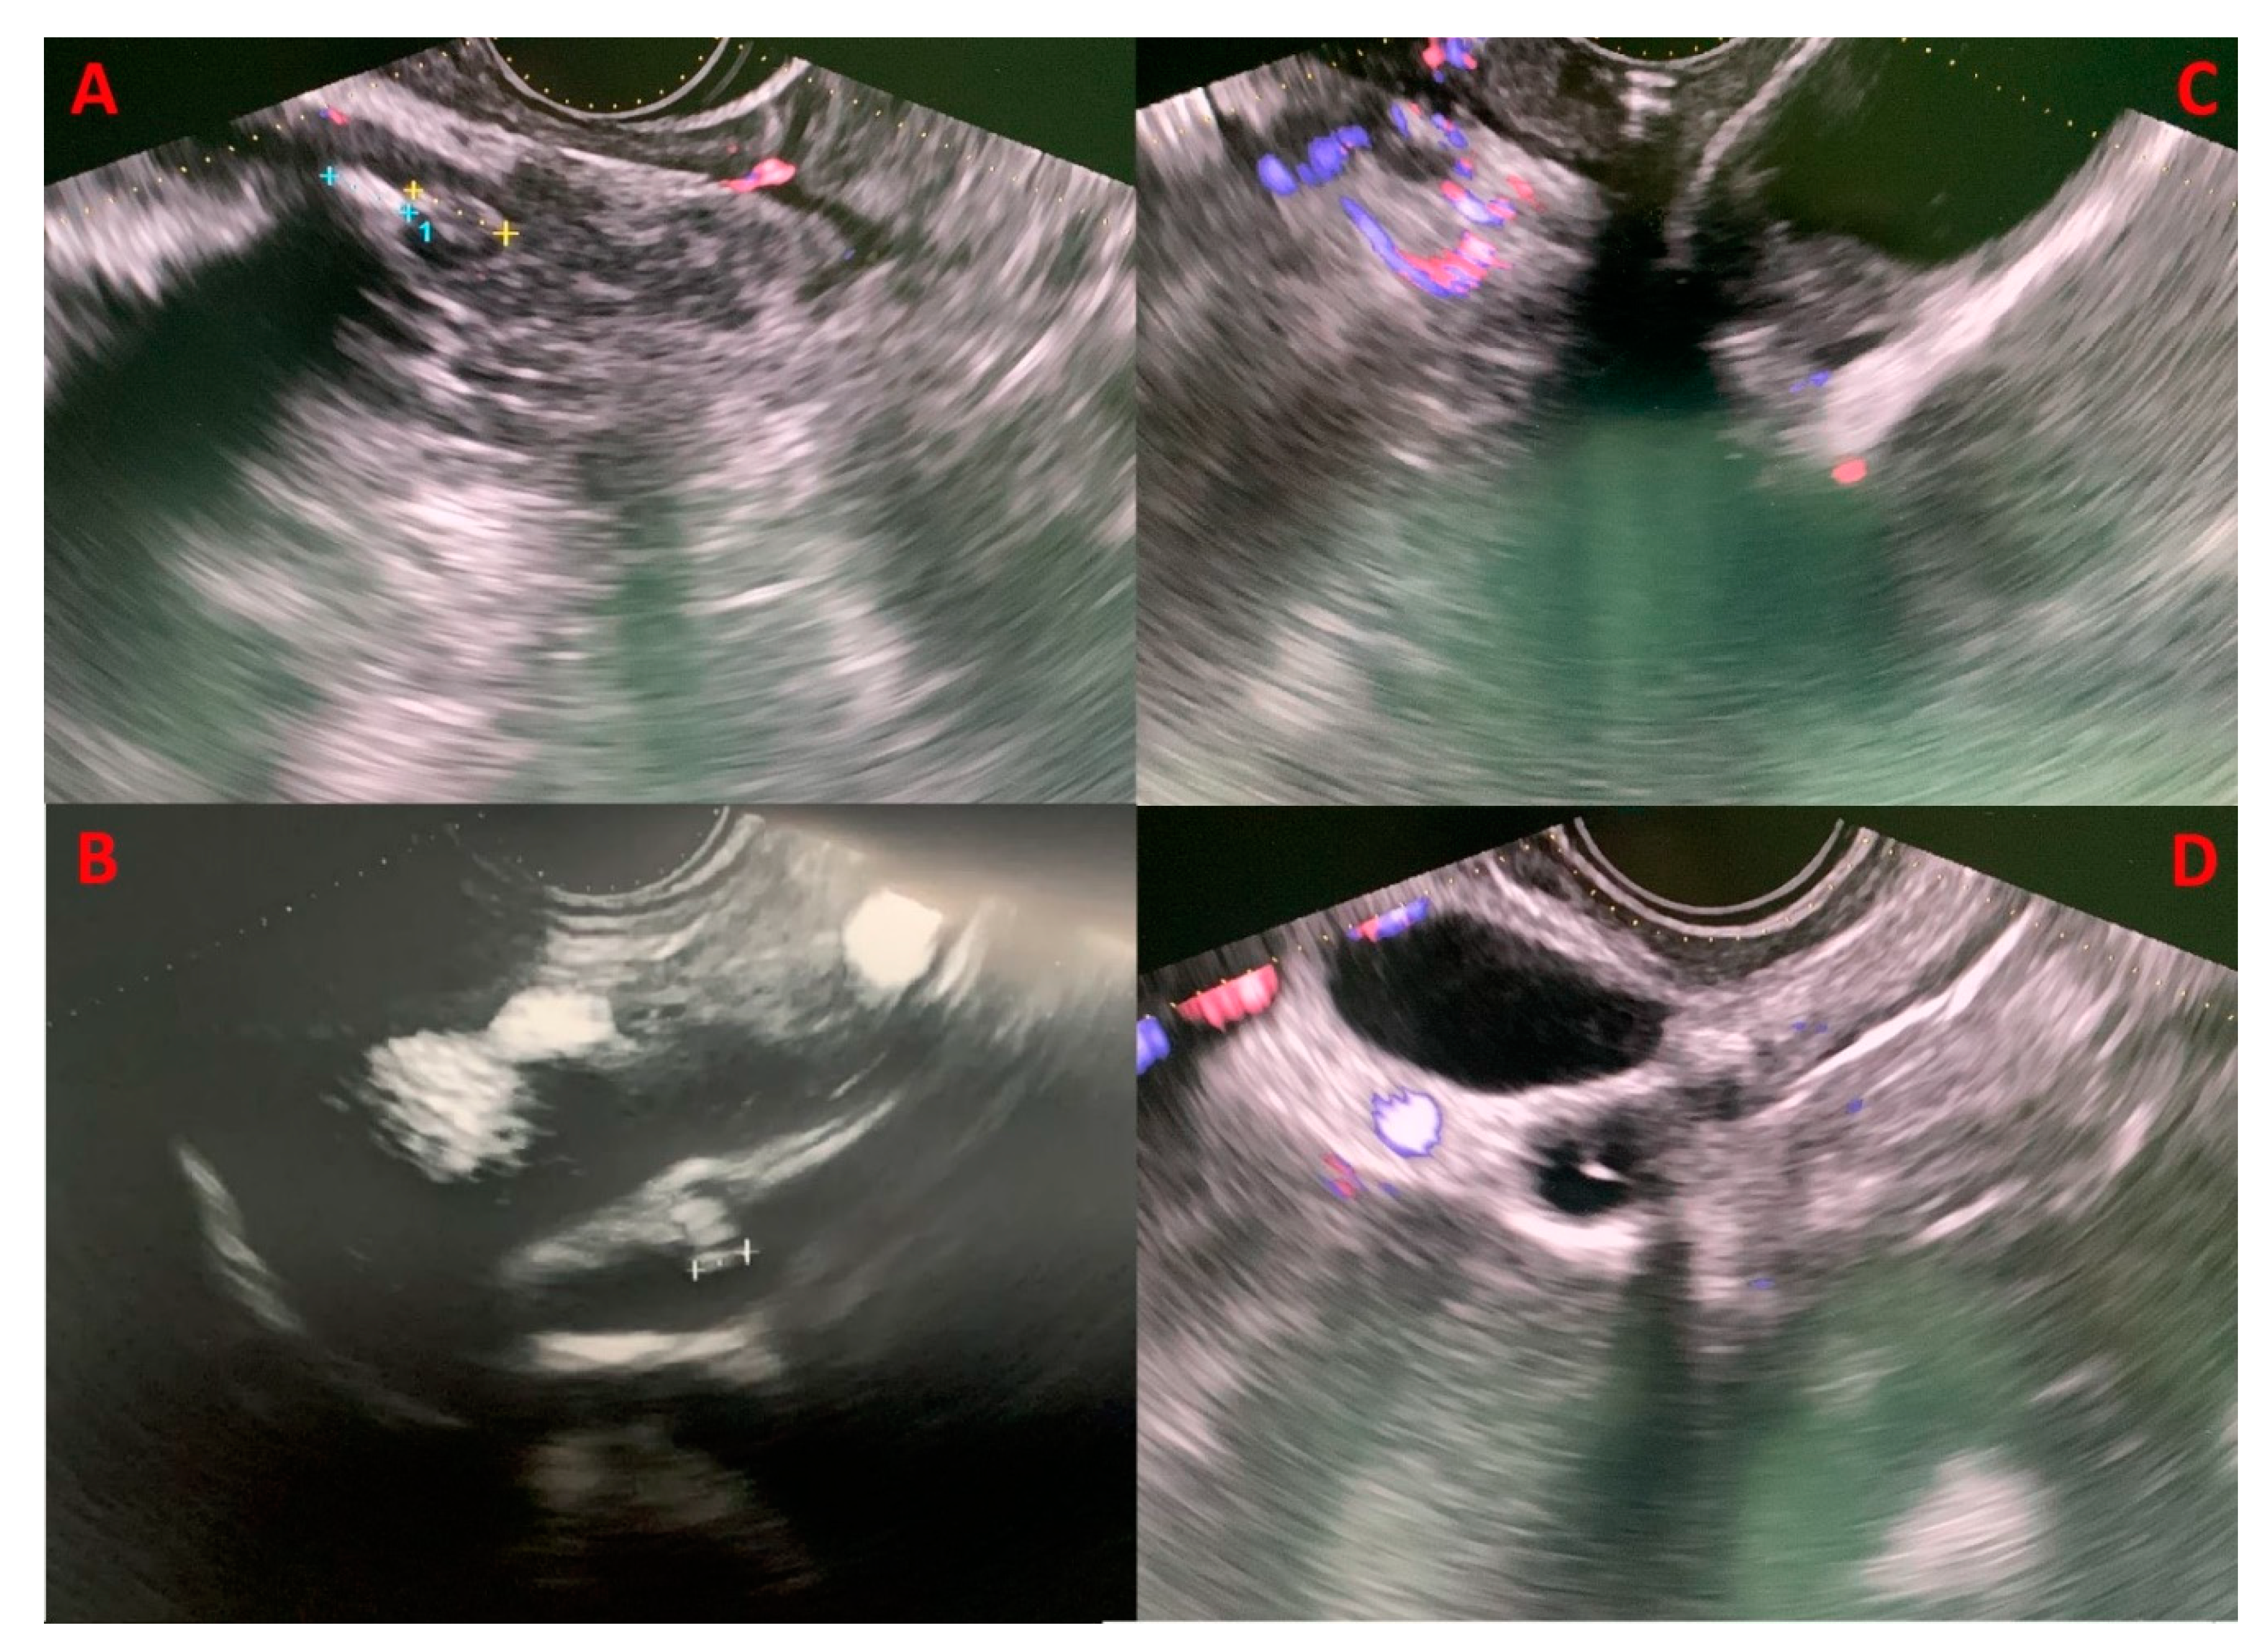

3.3. Role of EUS in biliary pancreatitis

Recent data suggested that with EUS, a biliary aetiology could be established in 37% of IAP patients [23,25,41,42,43,44,45,46,47] (Figure 2). When a biliary cause is found, it should be treated with ERCP, laparoscopic cholecystectomy (LC) or both. Some centres even recommend empiric LC in patients after single or recurrent attacks of IAP due to possible occult biliary disease [29,30]. There is an association between elevated ALT levels and acute biliary pancreatitis, with a positive predictive value of 85% for ALT>150 U/L within 48 hours after the onset of symptoms. Therefore, elevated ALT levels in IAP are strongly suggestive of a biliary aetiology [31,32,33]. Even if LC could be beneficial in such cases where the cause was microlithiasis or biliary sludge that was not identified, EUS can rule out other rare causes of, A.P. A thorough investigation of the patient’s biliary anatomy with MRI and EUS could identify rare conditions that could cause a pancreatitis recurrence or some conditions that if left untreated would give the patients higher morbidity and mortality, such as chronic pancreatitis, pancreas divisum, pancreatic neoplasm, cystic neoplasm, IPMN, pancreatic duct stones, pancreatic duct strictures, and other anatomic abnormalities [25]. IAP has indeed a relatively high recurrence rate, up to 25% during the 3 years after the first episode [34]. Chronic pancreatitis seems to be more frequent in patients with recurrent IAP, and it could be the manifestation of progressive organ damage from recurrent episodes of IAP [35].

Figure 2. Four clinical cases of biliary microlithiasis without retrodilatation of the common biliary tract, detected using EUS that were not identified in previous diagnostic examinations (transabdominal, U.S.; CT, and MRCP). Panels A and B display microcholedocholithiasis in the intrapancreatic and prepancreatic segments, respectively. Panel C highlights the presence of gallbladder sludge, while panel D demonstrates microlithiasis in the cystic duct stump.